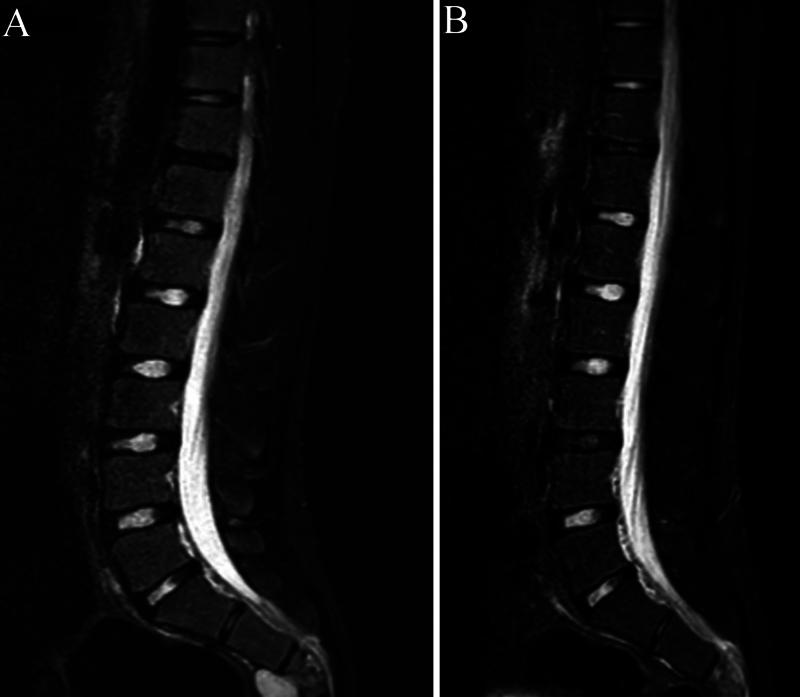

A 17-year-old male with a history of HC disease presented with low back pain radiating to both lower limbs, claudication, and chronic constipation for 5 years. Imaging revealed a large, multiloculated sacral cyst extending retrorectally and presacrally from S3 to S5, involving the spinal canal, compressing the rectum, and causing sacral erosion. A diagnosis of sacral hydatidosis was made, and the patient was started on albendazole, with surgical excision planned.

一名有HC病病史的17岁男性,出现下背部疼痛并放射至双下肢、间歇性跛行及慢性便秘达5年。影像学检查显示一个巨大的、多房性骶骨囊肿,从S3至S5向直肠后方和骶骨前方延伸,累及椎管,压迫直肠,并导致骶骨侵蚀。诊断为骶骨包虫病,患者开始服用阿苯达唑,并计划进行手术切除。